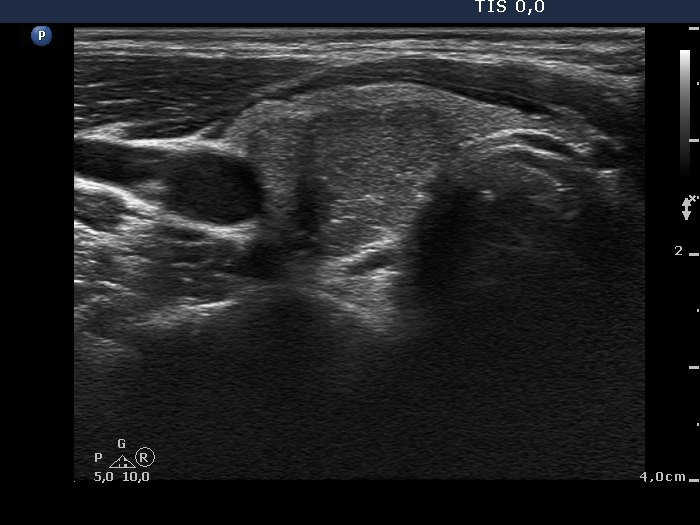

Benign hyperplastic nodules (histological diagnosis) - case 444 |

Papillary carcinoma (histological diagnosis) - case p002 |

Both lesions contain bright granules and lines, i.e. proliferation of connective tissue. The simultaneous presence of punctate echogenic foci (microcalcifications) cannot be excluded in either case. The ultrasound presentation differs in the shape and borders of the nodules. In contrast with the benign lesion, the malignant nodule is lobulated and has blurred borders in its dorsal part.